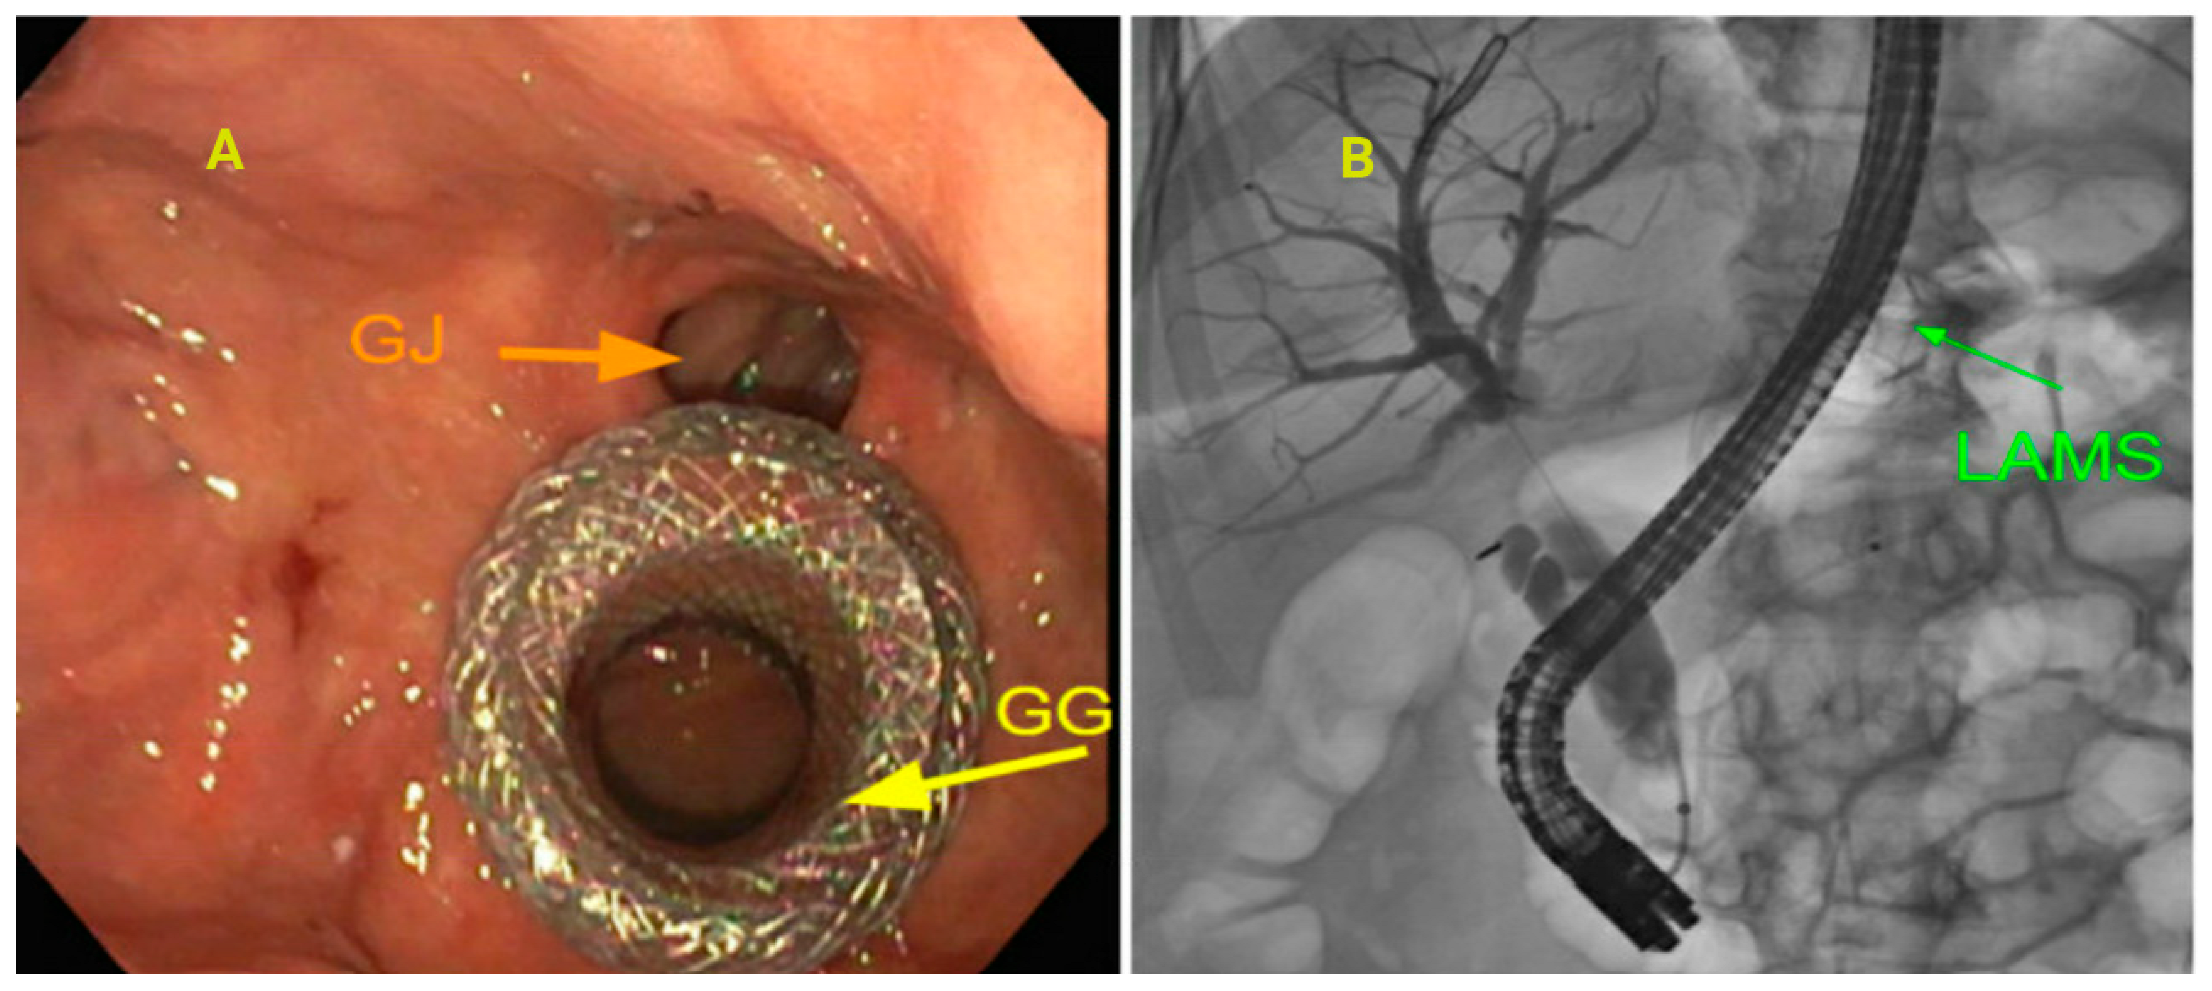

3.7. Altered Anatomy